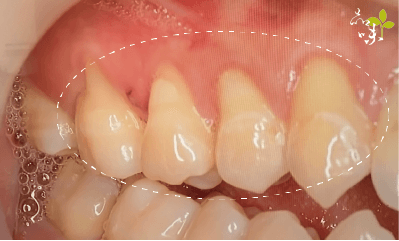

「冬天吃火鍋、夏天喝飲料,牙齒總是痠痛敏感,後來我才注意到,牙齒下方的牙肉消失了,露出黃黃的一截,以為是生病了,才趕快來掛號檢查。」你也有過類似的經驗嗎?很多人大約從20幾歲開始,就有牙齦萎縮的困擾了。這篇文章我們想跟你分享的是牙齦萎縮的成因,以及改善的方法。

牙齒剛生長出來時,牙根是被牙肉緊緊包圍的,只有上部的牙冠會露出牙肉表面。

某天,牙肉開始「倒退」、「減少」,讓牙根逐漸裸露出來,照鏡子一看感覺牙齒變長了──可能就是我們常講的「牙齦萎縮」現象。